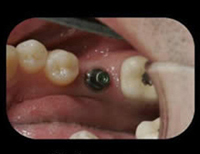

The Patient wears a "healing cap" while the implant integrates with the bone. Typically three to six months.

The doctor removes the "healing cap" to place the abutment, then takes an impression of this to send the lab to make your new crown.

The abutment act as a connector between the actual implant and the new crown.